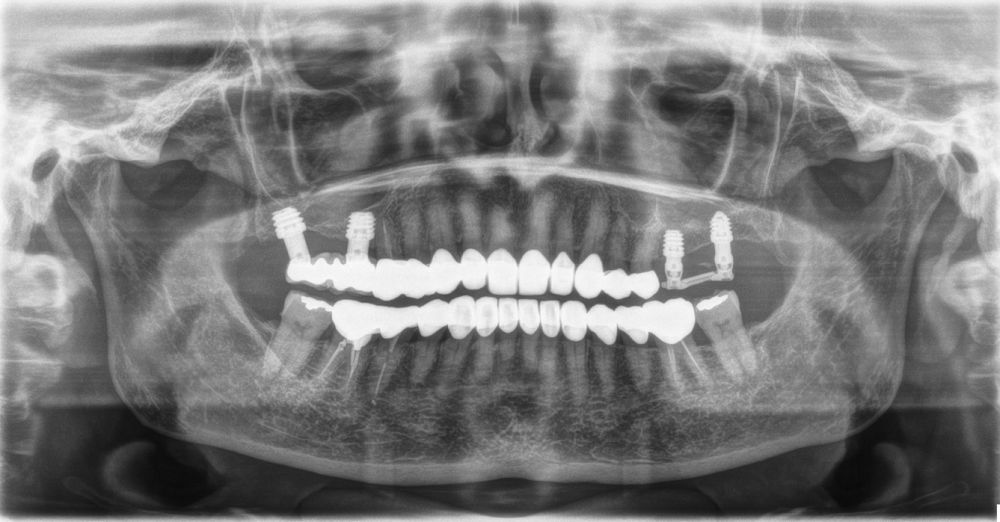

Material y método. Se ha llevado a cabo un estudio retrospectivo de pacientes tratados mediante implantes extracortos (5,5 y 6,5 mm de longitud) colocados mediante elevación transcrestal sin el uso de injerto. Como variables principales se han estudiado: la pérdida ósea crestal de los implantes y la ganancia en altura sobre el ápice. Como variable secundaria se ha estudiado la supervivencia de los implantes.

Resultados. Fueron reclutados 13 pacientes en los que se insertaron 30 implantes. Una vez insertados y cargados los implantes, la altura media final fue de 9,68 mm (+/- 2,66), lo que supone una ganancia promedio de 5 mm. A los 10 años, se observó una disminución media de la altura ósea ganada en los implantes en conjunto de 0, 29 mm (+/- 0,77). La media de la pérdida ósea mesial fue de 0,73 mm (+/- 0,75 mm) y la media de la pérdida ósea distal fue de 0,98 mm (+/- 1,2 mm). La supervivencia fue del 100%.

Material and methods. A retrospective study of patients treated with extra-short implants (5.5 and 6.5 mm in length) placed by transcrestal elevation without the use of a graft was carried out. The main variables studied were: the crestal bone loss of the implants and the gain in height above the apex. Implant survival was studied as a secondary variable.

Results.Thirteen patients were recruited and 30 implants were inserted. Once the implants were inserted and loaded, the mean final height was 9.68 mm (+/- 2.66), which represents an average gain of 5 mm. At 10 years, there was a mean decrease in the overall bone height gain of the implants of 0.29 mm (+/- 0.77). The mean mesial bone loss was 0.73 mm (+/- 0.75 mm) and the mean distal bone loss was 0.98 mm (+/- 1.2 mm). Survival was 100%.

Nuestro grupo de estudio modifica esta técnica de elevación transcrestal utilizando para el acceso unas fresas de corte frontal que permiten eliminar la cortical inferior del seno con lentitud sin dañar la membrana de Schneider, eliminándose los osteotomos y el malestar que genera su accionamiento mediante el martillo6-7. Inicialmente el procedimiento fue concebido para ser empleado con material de injerto al igual que el abordaje convencional, pero posteriormente se presentaron variaciones del procedimiento donde se insertaban los implantes sin injerto, utilizándose el propio implante como mantenedor de espacio entre la membrana de Schneider y la cavidad creada entre la membrana y la cresta, permitiendo que esta cavidad no se colapsase y posteriormente fuera colonizada por nuevo hueso7-11.

Los senos tratados con la técnica de elevación transcrestal sin material de relleno muestran un incremento de entre 2,5 mm12,13 hasta 4.4 mm14,15 en la altura ósea lograda sobre el ápice y una supervivencia de los implantes que se sitúa entre un 94 y un 100%16-17. En este trabajo se presenta un estudio retrospectivo donde se ha evaluado la inserción de implantes extracortos (5,5 y 6,5 mm) en zonas posteriores maxilares mediante la técnica de elevación de seno transcrestal con la fresa de ataque frontal sin la utilización de material de injerto, con un tiempo de seguimiento de 10 años para poder objetivar el comportamiento de los implantes a largo plazo y de la técnica empleada.